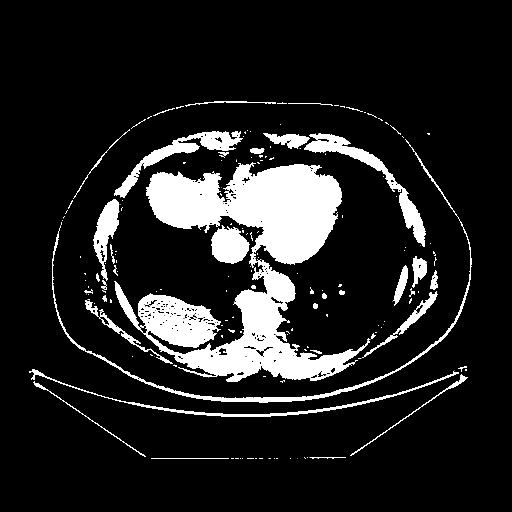

Original VENOUS CT scan

Full window (WL 1023.5, WW 4095 β†’ Low βˆ’1024, High +3071)

Actual HU range: [-1024.0, 3071.0]